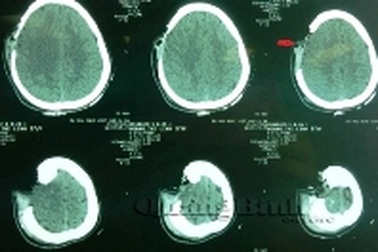

Chờ ghép lại, mảnh xương sọ được nuôi bằng bụngChiều 28/4, tin từ các bác sĩ Bệnh viện Hữu nghị Việt Nam - Cu Ba Đồng Hới cho biết, sau ca mổ cấp cứu, bệnh nhân bị văng ra ngoài 1 một mảng xương sọ kích thước khoảng 10x12cm đã qua cơn nguy kịch.